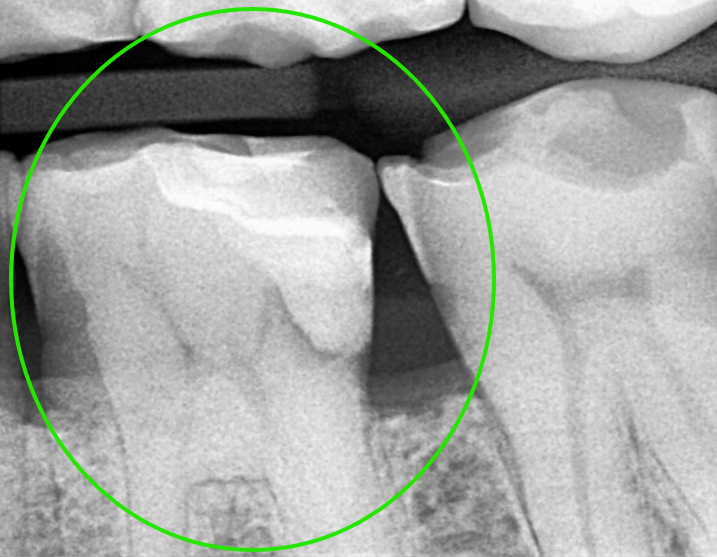

Were you told a cavity is too deep to fix? Using Microscopic Deep Margin Elevation and Dual-Laser Technology, we preserve your natural tooth structure and avoid aggressive extractions.

Don’t Cut the Gum. Elevate the Tooth.

Traditional dentistry often requires painful surgery (Crown Lengthening) to reach decay below the gumline. Our DME Protocol is a non-surgical alternative. We “elevate” the floor of your cavity using bioactive materials, keeping your tooth intact and your gums health